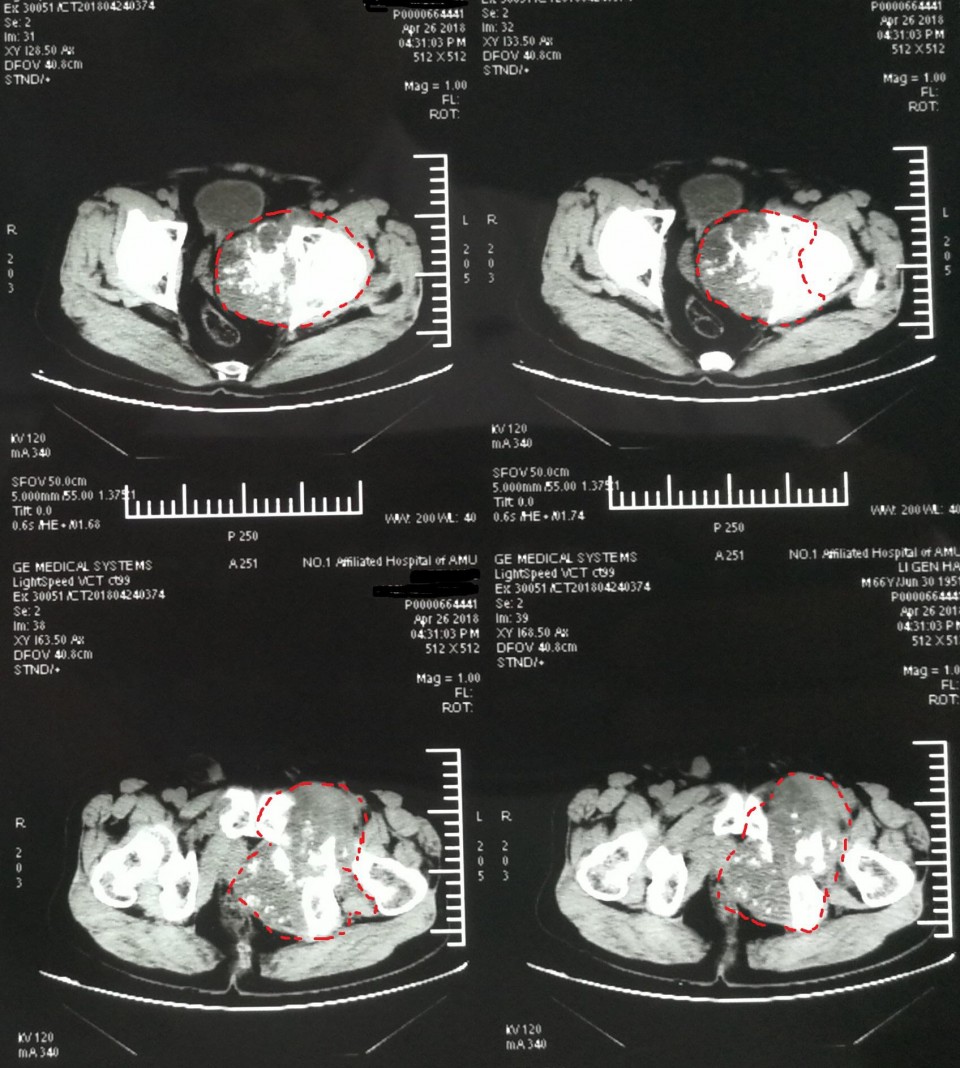

日前,骨病骨肿瘤科近日完成 “骨盆Ⅱ+Ⅲ区巨大软骨肉瘤行内半骨盆切除+股骨头旷置术的保肢治疗 ”1例。患者66岁男性,髋部疼痛不适3月余入院,经检查提示骨盆Ⅱ+Ⅲ区巨大恶性骨肿瘤。骨盆的恶性肿瘤,往往就诊时肿瘤已经发展了相当长的时间,而肿瘤巨大、术中出血多、局部解剖结构复杂等因素使得手术难度及风险增高。早年对骨盆恶性肿瘤的治疗,半骨盆截肢术是骨盆恶性肿瘤的主要治疗方式。但患者所承受的心理压力巨大,面对肢体残缺所引起的恐慌使其拒绝接受治疗,尤其对于年轻患者。保肢术的开展及应用为这些患者带来希望,但手术难度极大,不易达到安全的外科边界。胡勇教授团队根据患者病情,制定精细手术方案,多套手术预案,由于患者经济条件不佳,使用人工关节假体会造成患者极大负担,而且如果出现并发症需要治疗,更导致花费巨大。采用内半骨盆切除+股骨头旷置术,术中既完整的切除了肿瘤,又保全了半侧肢体,辅助术后功能锻炼,几乎可以达到与人工假体相媲美的肢体功能。患者术后顺利康复出院。

胡勇教授指出,骨盆肿瘤的规范化治疗中,肿瘤的完整切除在其治疗中占重要地位,由于骨盆位置深在,血管神经、肠道泌尿道毗邻,骨盆肿瘤的完整切除手术难度极大,技术要求高。对于肢体的重建,虽然人工假体并发症多、价格高昂,但能提供患者相对较好的髋关节功能,肢体长度和外形较满意,故对于大多数患者来说,只要局部软组织重建条件允许骨盆人工关节置换仍是首先考虑的重建方法。该患者由于经济原因不能承受人工假体高昂的费用支出,我们手术尽量保留髋臼顶部骨量,将股骨头置于该处,后期形成假关节可替代原髋关节保留行走功能。一些学者经过长期随访研究,认为旷置成形术避免了很多严重并发症,而且创建了一个无痛且有中等程度功能的肢体。类似骨盆肿瘤的手术我科已开展多例,均取得良好疗效。